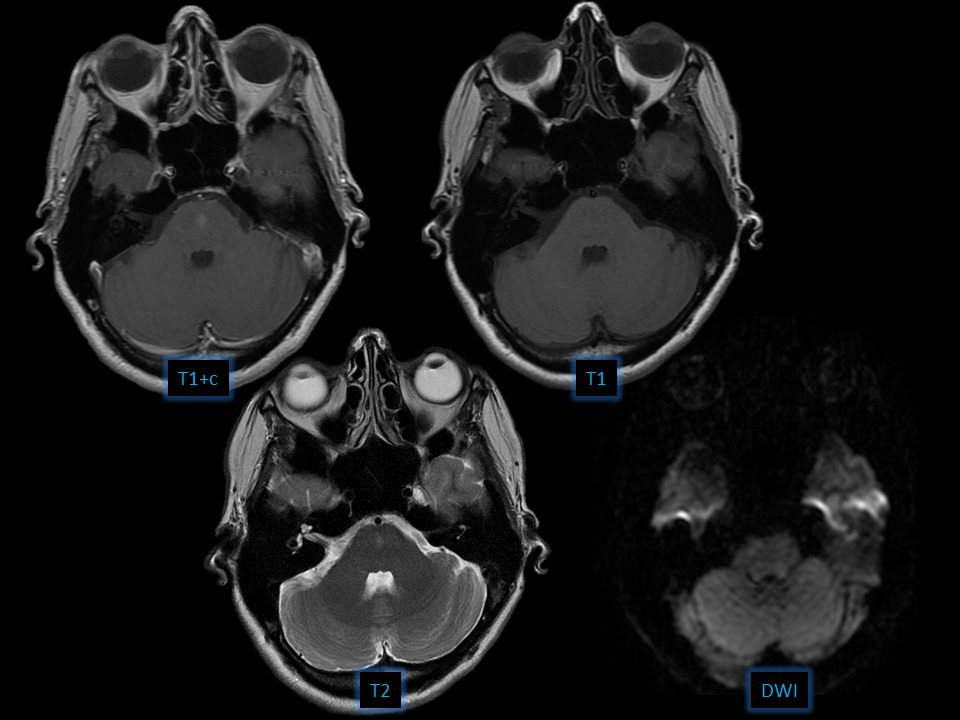

Findings – Central pontine enhancing focus – No mass effect Differential – Capillary telangiectasia – Developmental venous anomaly – Metasta...

Findings

– Central pontine enhancing focus

– No mass effect

Differential

– Capillary telangiectasia

– Developmental venous anomaly

– Metastasis

– Cavernous malformation

Diagnosis: Brain capillary telangiectasia

• Cluster of enlarged capillaries with interspersed parenchyma

• Enhancement without mass effect

• 50% T2 hyperintense

• Common locations

-Pons

-Cerebellum

-Spinal cord